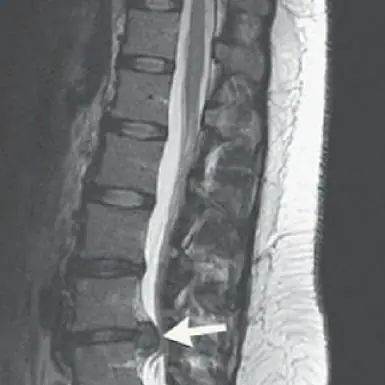

Vertebral Compression Fractures occur when a vertebral body in the spine collapses leading to pain, deformity and loss of height.

Kyphoplasty and Sacroplasty for Compression Fracture

Kyphoplasty is a minimally invasive spinal procedure that treats pain due to acute vertebral compression fractures